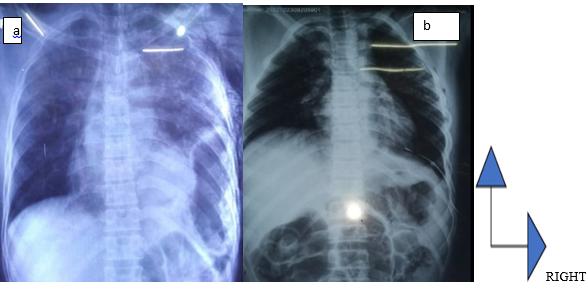

An 18-year-old patient with no known pathological history, was admitted to the emergency room for multiple trauma associating: closed thoraco-abdominal trauma, firm trauma of the left arm and a closed trauma of the contralateral leg. On admission, he was conscious, well-oriented in time and space with Glasgow 15/15. The patient was noted to be unstable in terms of hemodynamics (BP = 90/60 mm Hg and HR = 124 beats / minute) and ventilation (FR = 32 cycles / minute and spo2 = 88 % in room air). There were also dermabrasions on the left hemithorax and opposite the left hypochondrium, asymmetry of the thorax, and decreased amplification of the left thorax. On auscultation, vesicular murmurs were absent in the left pulmonary field replaced by hydro-aeric sounds. On abdominal examination, the abdomen is soft and painless to palpation and hydro-aeric sounds are heard on abdominal auscultation. Examination of the musculoskeletal system reveals a fracture syndrome of the left arm and a fracture syndrome of the right leg. The frontal chest X-ray had objectified a hydro-aeric image occupying the left hemi-thorax and pushing the diaphragmatic dome upwards. The mediastinal structures were pushed towards the contralateral side. The X-ray of the left arm had objectified a closed fracture of the humerus and the X-ray of the right leg objectified a closed fracture of both legs. The chest CT scan was not performed. The biological assessment was unremarkable. We performed surgical exploration by supra-umbilical median laparotomy. The exploration found a 7 cm rupture of the fleshy portion of the left diaphragmatic dome and abdominal viscera (greater omentum, stomach). We proceeded to reintegrate the organs with a suture of the diaphragmatic defect by separated stitches with non-resorbable thread 0. Osteosynthesis was performed at a later time for limb fractures. The postoperative course was simple. Chest X-ray on postoperative day 2 showed the disappearance of the initial lesions (Figure 3b). The chest drain was removed on postoperative day 4. The patient was discharged from the hospital on postoperative day 5. After 6 months, no complaints were reported by the patient.

Figure 3 Frontal chest X-ray showing a left intrathoracic hydroaeric image with ascension of the diaphragmatic dome (a). Postoperatively, disappearance of the hydroaeric image with re-amplification of the left hemi-lung (b).